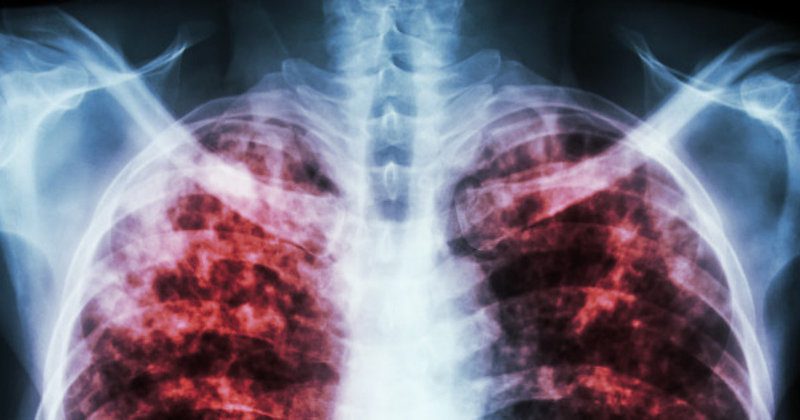

Як виявилося, не профінансовано майже нічого. Чи не забезпечені майже нічим. Ну а про здатність вилікувати що-небудь важче банального неускладненого ГРВІ (і то не завжди) говорити навіть смішно. Реформа від Уляни Супрун остаточно підкосила медицину на всіх без винятку рівнях, але особливо сильно дісталося спеціалізованим стаціонарам. Вони були засновані і існували не просто так, заради розваги, а тому, що ті хвороби, від яких лікували в їх стінах, являють собою особливу небезпеку для оточуючих. Яскравим прикладом тому може служити туберкульоз – дуже контагіозне (заразне) інфекційне захворювання,що часто приводить до смерті або інвалідизації хворого (а при відсутності своєчасного адекватного лікування – майже завжди). У здоровому розумі і тверезій пам’яті ніхто з нас не хотів би їздити з хворим на сухоти (саме так раніше називали туберкульоз) в транспорті, слухати його кашель із задишкою із сусідньої квартири, робити покупки в тих же магазинах, і так далі. Але в уряду реформаторів для вас погані новини. З першого квітня, тобто рівно два тижні тому, три з чотирьох протитуберкульозних диспансерів в Запоріжжі закрилися назавжди. В єдиному, що залишився, скоротили кількість ліжок – більш ніж в два рази – гуляти так гуляти. Медичний персонал (кваліфіковані і досвідчені лікарі, медичні сестри та відповідальні санітарки) здебільшого вигнані на вулицю (не вписалися в ринкову економіку і реформу, так би мовити), а іншим обіцяють платити в кращому випадку мінімалку. З огляду на ризик для життя, вони звільняються самі. Просто кладуть заяви на стіл.

Хворі надані самі собі. Їх виписали зі стаціонарів (кілька сотень людей, до речі) і розпустили по домівках. Магазини, транспорт, школи і садочки після карантину – зустрічайте! За статистикою, в середньому один хворий на відкриту форму туберкульозу може заразити до десятка здорових до (увага!) виявлення і потрапляння на лікування. Оскільки потрапляти вже нікуди, все закрито, цифру сміливо множте на … А хто ж його знає? На багато. Там, де був один хворий, стане сотня. Де було кілька сотень виписаних зі стаціонару – рахуйте самі, вже дуже похмуро виходить. При функціонуючій системі протитуберкульозних диспансерів Україна як могла стримувала оголошену у нас Всесвітньою організацією охорони здоров’я епідемію туберкульозу. Тепер, мабуть, не зможе.